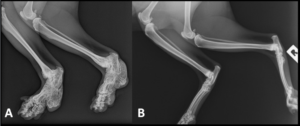

Bone abnormalities in Scottish Fold cats: ‘A’ shows a severely affected cat and ‘B’ a mildly affected cat (photo courtesy of Richard Malik)

- Osteochondrodysplasia (OD): This condition is linked to the genetic mutation responsible for the folded ears. It affects the development of cartilage and can lead to abnormal bone and joint growth. Cats with severe OD can experience pain, lameness, and difficulty moving if you Breed two folded-ear cats together, which can result in offspring with more severe forms of this condition.